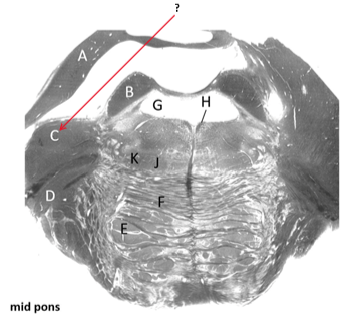

Name this and state its function.

Transverse pontine fibres.